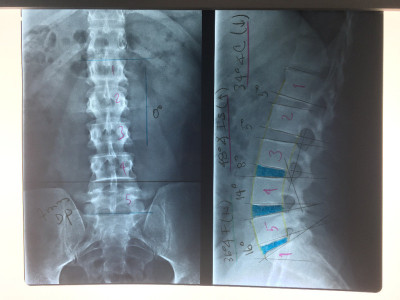

Artroplastía lumbar y prótesis de columna

Envíado por Dr. Hugo Enrique Castro Cordero